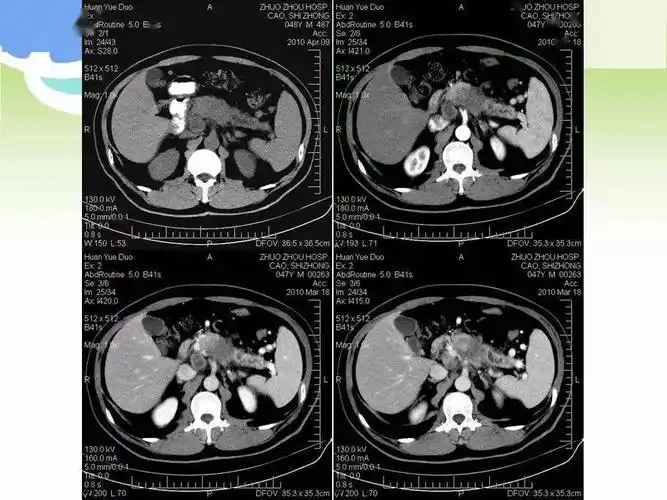

【病例】胰腺癌1例ct影像表现

患者因胃部不适至医院检查,无意中发现胰腺肿瘤,pet/ct提示胰腺癌伴肝

ct等相关检查后,医生发现患者胰头部占位病变,考虑到胰腺癌可能性大

胰头清晰,颈部稍长t2信号胰腺癌ct增强扫描:胰腺头部,体尾部早期均匀

【读片】胰腺癌 [病例帖]